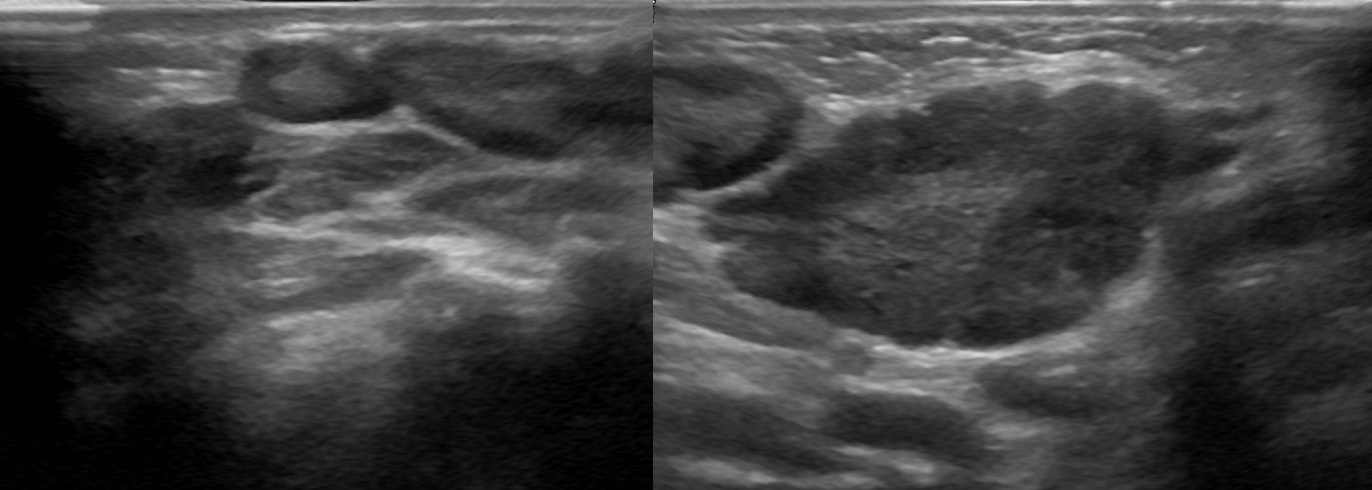

УЗИ лимфоузлов при лимфоме Ходжкина

Раздел: Образы вокруг